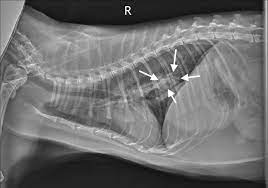

Lung Cat No 1 Diffuse Severe Bronchointerstitial Pattern Download Scientific Diagram

Lung Cat No 1 Diffuse Severe Bronchointerstitial Pattern Download Scientific Diagram from www.researchgate.net